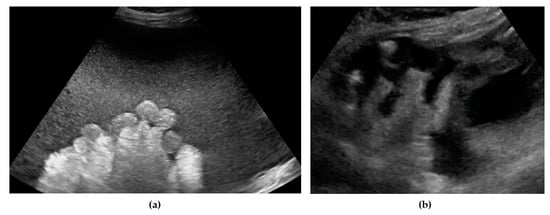

| Ascites | Fluid outside the pouch of Douglas, recorded as being present or absent 1 | Figure 5 | Video S5 |